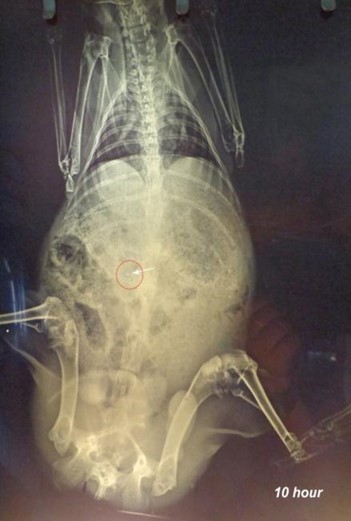

X-ray studies revealed that the microspheres remained in the stomach for the first 2h as shown in fig. (7). Microspheres get released from the capsule shell by dissolving the gelatin shell and distributed in the small intestine as observed in the fig. (8).

Since the particles are small, and the amount of radio-opaque material is also less, the amount of microspheres visible by X-rays is also minimal. Microspheres are visible at 4th h in the small intestine as observed in fig.(8), and some are also seen in the X-ray image taken at the 8th h in the large intestinal region [22]. X-ray image at 10th h indicates the presence of microspheres in the colonic region as seen in fig.(10). The observations were confirmed by a veterinary surgeon. It can be concluded that the formulation is able to target colonic region effectively.

Fig. 10: X-ray image after 10 h